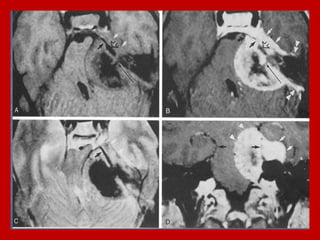

choroid plexus papilloma (CPP) at the 4th

and 3rd ventricles (Ct and MRI images

choroid plexus papilloma, MRI images